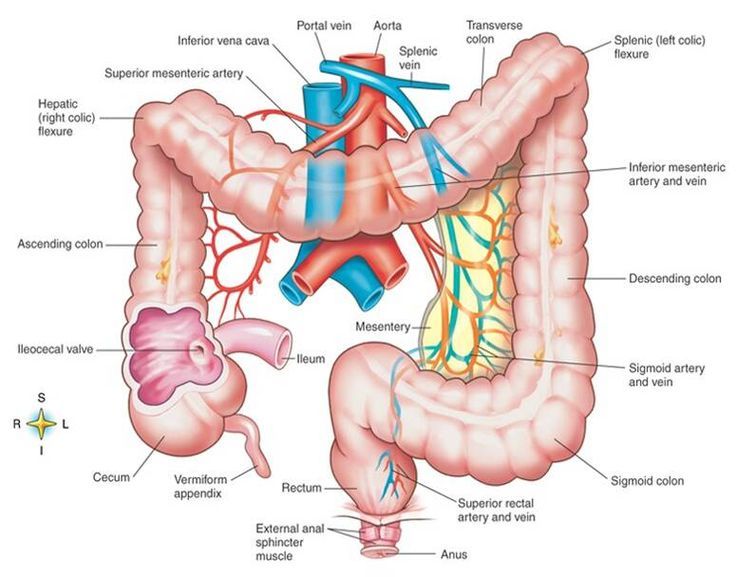

The appendix arises from the posteromedial surface of the cecum, approximately 2-3 cm inferior to the ileocecal valve, where the three longitudinal bands of the taeniae coli converge. It is a blind diverticulum which is highly variable in length, ranging between 2 and 20 cm. The appendiceal mesentery is called the mesoappendix 1,2.

The appendix is a narrow blind-ended tube that is attached to the posteromedial end of the cecum (large intestine). It contains a large amount of lymphoid tissue but is not thought to have any vital functions in the human body.. In this article, we shall look at the anatomy of the appendix - its anatomical structure and relations, neurovascular supply and lymphatic drainage.